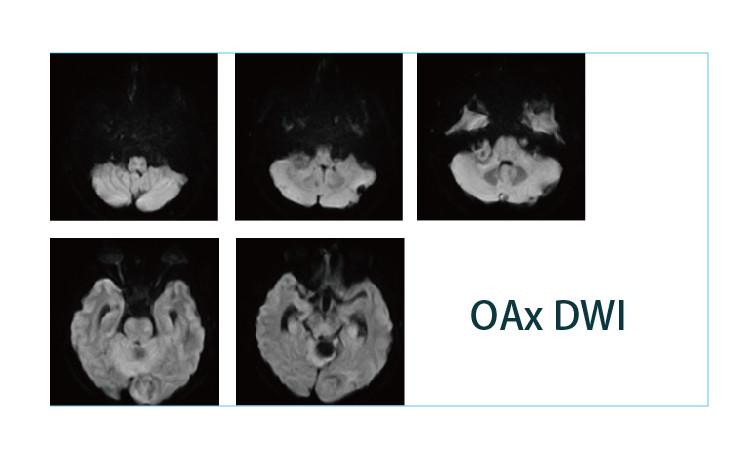

【朗润影像档案】20190412磁共振影像病例结果讨论

【朗润影像档案】磁共振影像病例分享(编号20190412)